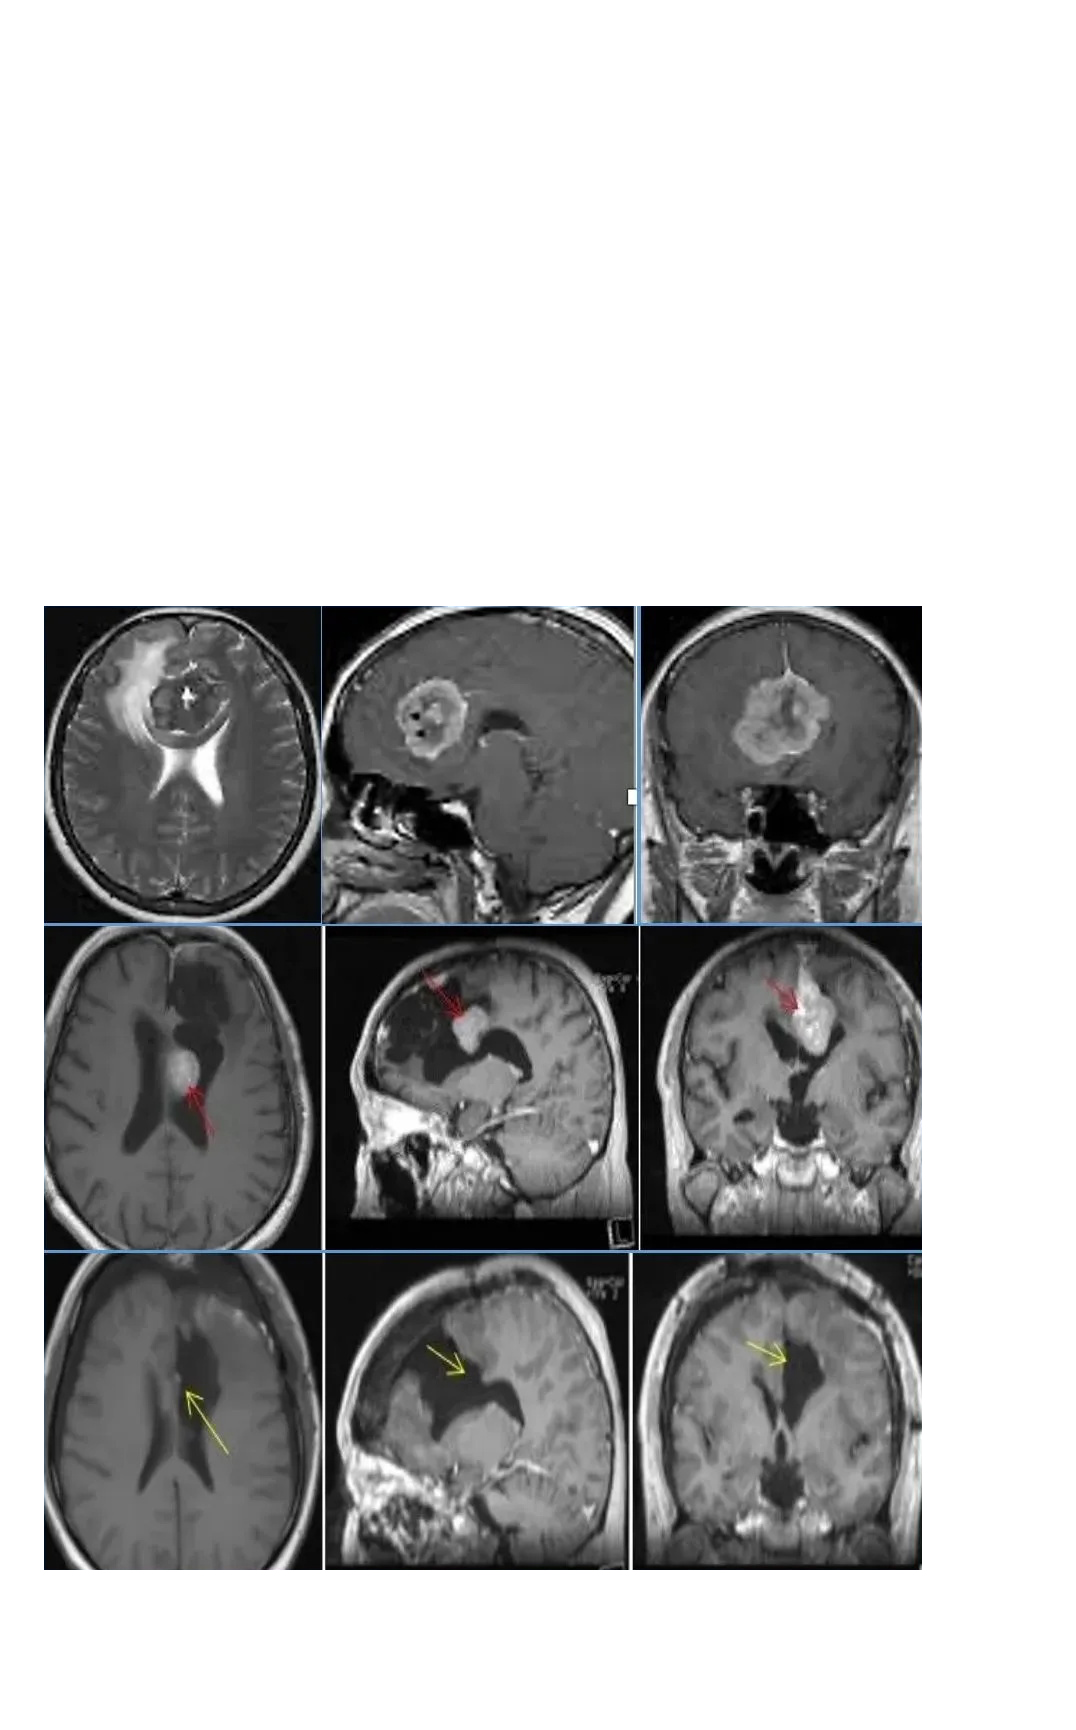

脑膜瘤伽马刀治疗无效,一台手术顺利全切

术前情况:2021年9月,50多岁的钟女士在体检中意外查出CPA区脑膜瘤。当时医生告诉她,右侧桥小脑角(CPA)区占位,肿瘤位置附着岩谷、临近面听神经,且已经压迫脑干,手术治疗伤及神经的风险很大,也就是说如果手术做不好,钟女士可能以后开口吃饭、睁眼看东西的力气都没有了,也很可能失去视力和听力。

手术情况:2022年巴教授中国行中,成功主刀手术肿瘤全切,无新发神经功能损伤。术后一天ICU查房,钟女士状态清醒,和教授交流顺畅。术后五天查房,钟女士状态良好,连声感谢巴教授并和教授开心合影。病理结果脑膜瘤WHOI级,良性预后很好,术后将不再需要反复放化疗,她可以像正常人一样生活。

▼术前术后MRI对比

术后情况:术后10天,我们对患者爱人进行了采访,给相同经历的患者家庭带来一些合适的参考信息。

钟女士早已恢复了正常生活,术后进行定期的影像随访。术后九个月时,钟女士收到了巴教授回复的随访邮件,没有复发、无残留。